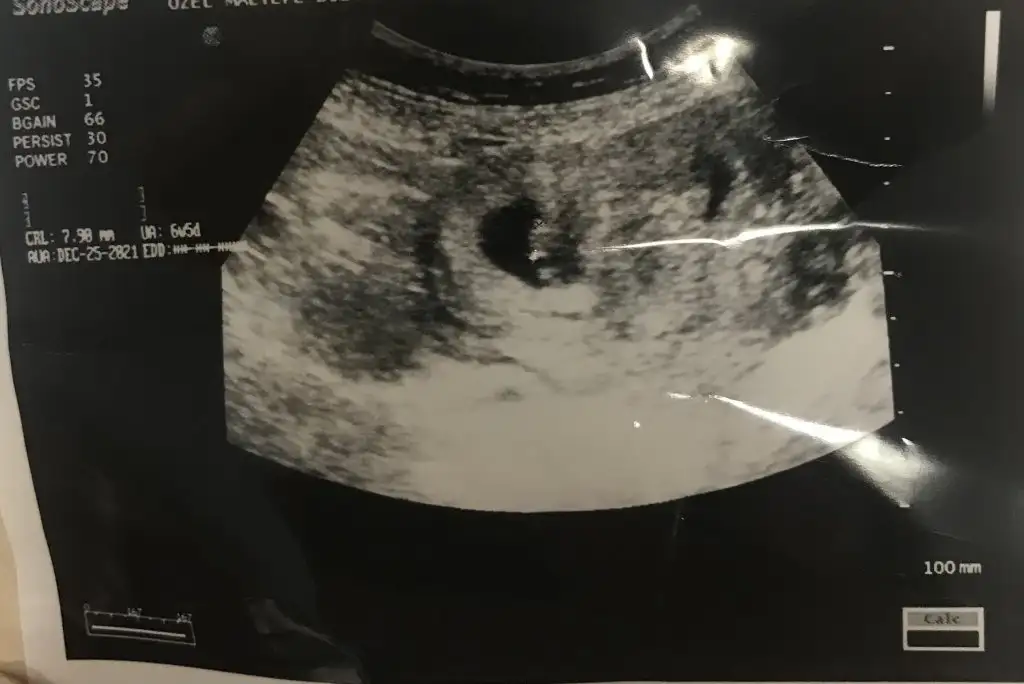

Mrb bakalım daha 10+4 olduk 9 Nisan'da 2 li taramaya gidicem attıgım resim 6+4 tü galibaMerhaba millet

Karından bu aradaMrb bakalım daha 10+4 olduk 9 Nisan'da 2 li taramaya gidicem attıgım resim 6+4 tü galiba

DAHA COK KUCUGUZ 4+3 ÇARSAMBA TEKRAR GİDECEĞİMÇOK HEYECANLIYIM KIZLAR ILK REMIMIZ